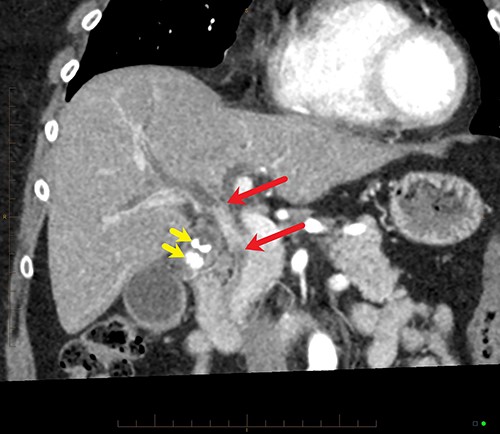

An ultrasound of the abdomen revealed a large gallstone in the gallbladder neck measuring 36 mm with mild biliary dilatation (Fig. 1). Magnetic resonance cholangiopancreatography (MRCP) revealed an irregular long stricture of the extrahepatic bile duct beginning distal to the primary biliary confluence, involving the common hepatic duct for a distance of 20 mm (Fig. 2). A multiphase liver magnetic resonance imaging was performed which confirmed a malignant appearing stricture of the common hepatic duct and showed an ill-defined soft tissue lesion in the porta hepatis between the gallbladder neck and the common hepatic duct (Fig. 3). Her Ca 19.9 was 160 kU/L (ref range < 35 kU/L).

Coronal MPR of late arterial phase CT reveals segmental common hepatic duct stricture with circumferential wall thickening and enhancement (between red arrows) resulting in intrahepatic duct dilatation. Radiopaque calculi (yellow arrows) in the gallbladder.